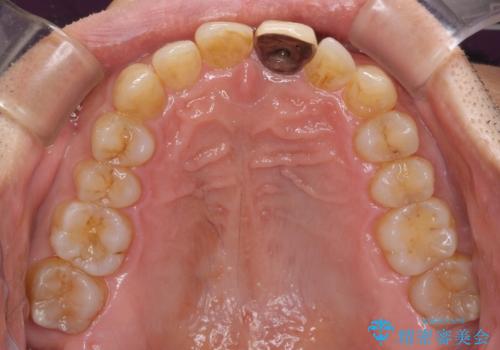

- 上下前歯のデコボコと下顎小臼歯の欠損によるスペースを気にして来院された患者様です。

下顎は左右1本ずつ小臼歯が欠損しており、右側にはやや大きな欠損がありました。

欠損により下顎歯列は相対的に小さく、上顎に深く咬みこんでしまうディープバイトとなっていました。

インビザラインによる治療を希望されたため、左側のスペースは閉じ、右側はスペースをより拡大し、インプラント補綴を行うこととしました。

咬合力が強く、インビザラインのみではディープバイトを改善することができず、半年間ほどワイヤー装置による矯正治療を行いました。

インプラントの埋入は矯正治療中に行い、矯正治療後はインプラント上補綴および、前歯のセラミック治療を行いました。